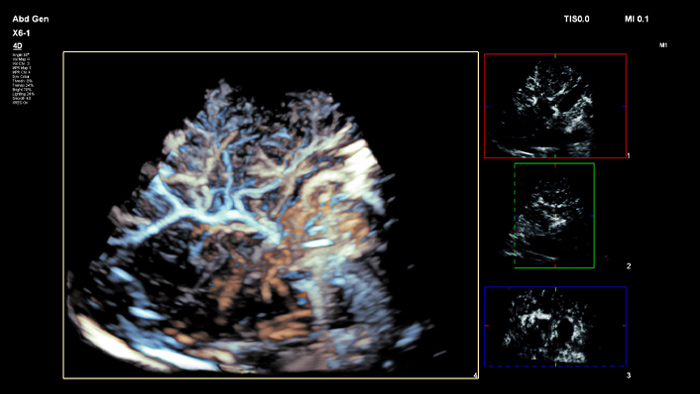

ElastQ bietet mit der 2D-Scherwellen-Elastographie (2D-SWE) eine nichtinvasive, reproduzierbare und einfach durchzuführende Echtzeit-Beurteilung der Gewebesteifigkeit. Außerdem beinhaltet ElastQ Imaging eine Funktion zur retrospektiven Messung an gespeicherten Bildern sowie eine entsprechende Darstellung der statistischen Sicherheit für die höchste Scherwellenausbreitung.

ElastQ Imaging